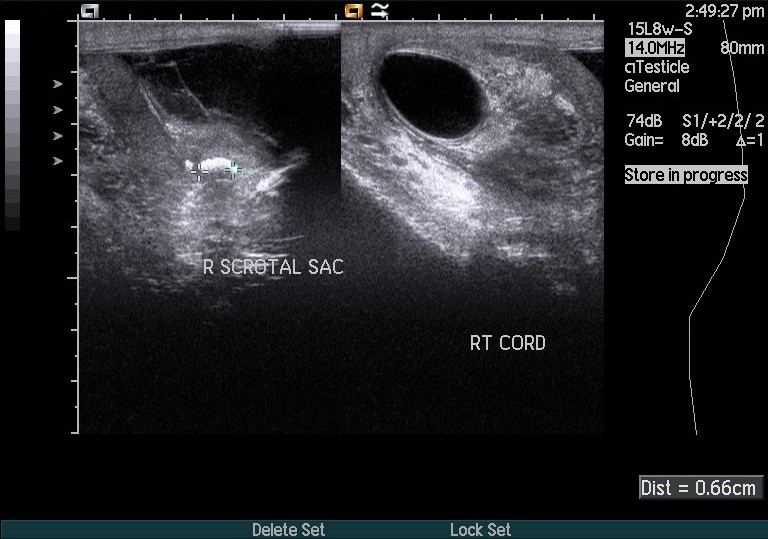

Normal Epididymis Ultrasound